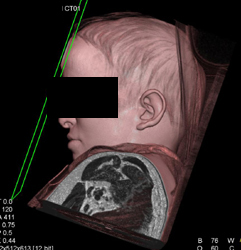

Diagnosis

Loeys-Dietz With Ectatic Vessels